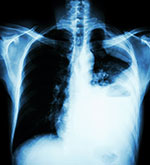

Breathing asbestos can cause tiny asbestos fibers to get stuck in the lungs and irritate lung tissues.

- Asbestosis is scarring in the lungs caused by breathing asbestos fibers. Oxygen and carbon dioxide do not pass in and out of scarred lungs easily, so breathing becomes harder. Asbestosis usually occurs in people who have had very high exposures over a long time, but years may pass before any symptoms appear.

- Pleural disease is a non-cancerous lung condition that causes changes in the membrane surrounding the lungs and chest cavity (pleura). The membrane may become thicker throughout (diffuse pleural thickening) or in isolated areas (pleural plaques), or fluid may build up around the lungs (known as a pleural effusion). Not everyone with pleural changes will have problems breathing, but some may have less efficient lung function.